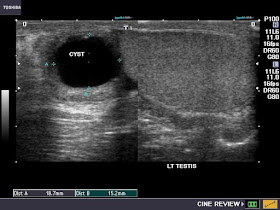

Left Epididymal cyst

Spermatoceles are the commonest cystic lesions of the scrotum. Both spermatocele and simple cysts of the epididymis are often difficult to distinguish from each other purely on ultrasound. The main difference is usually presence of echogenic debris or particles in the fluid within the cystic mass; particles (inactive sperms) are present in spermatocele (see images above) whilst clear fluid is seen in simple cyst of the epididymis (top most images).